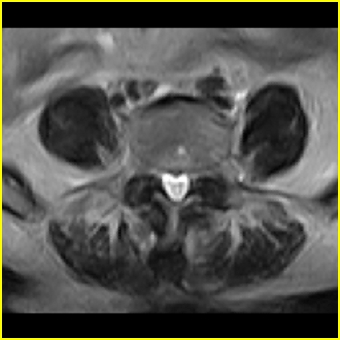

男,78岁,右下肢跛行两月.

右侧黄韧带肥厚或钙化,压迫马尾神经所致。必要时行ct扫描。

腰间盘膨出、黄韧带肥厚、可疑先天性腰椎管狭窄。